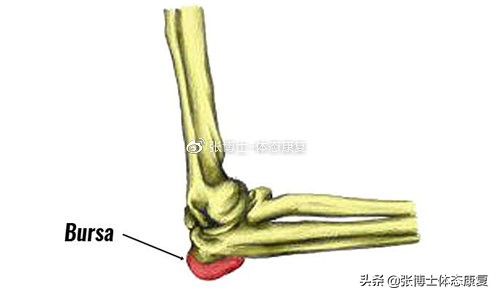

1.肘部滑囊炎

也称为学生肘,它是肘后部的滑囊出现炎症和肿胀。重复地撞击肘部的后部,例如长时间靠在桌子上就是一个常见的原因。随着时间的推移,粘液囊变得肿胀、疼痛、发炎。